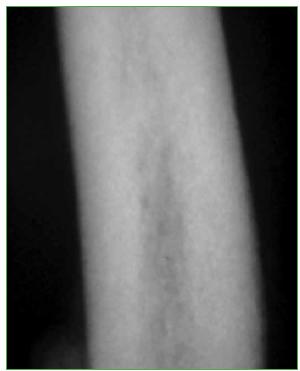

Figura 2.

Radiografía de diáfisis del húmero que muestra el aumento del espesor de la cortical.